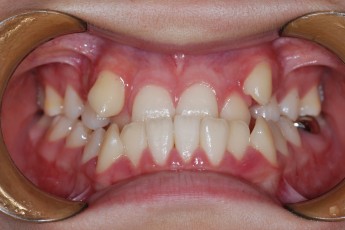

Before & After

Before

After